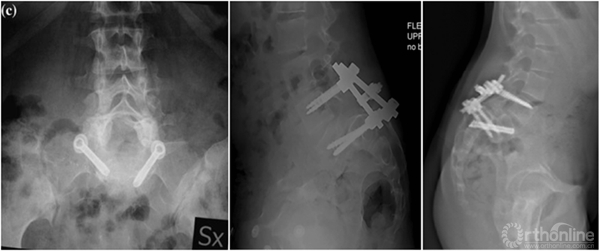

① 对于失平衡不重者,可以采取一期后路部分复位和经骶骨轴向融合方式[4]。

② 明显失平衡者,采取后路复位联合前路支撑重建术式。

② 我们的病例